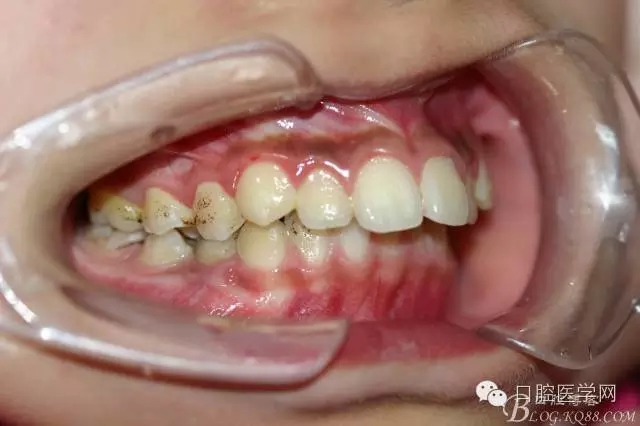

正畸查:替牙合。第一恒磨牙中性合。上牙弓尖圓型下牙弓方圓型。前牙覆合3度覆蓋7.5mm。下前牙咬到上舌側(cè)牙齦。上頜擁擠4.0mm,下頜擁擠

3.0mm。上頜稍前突下頜后縮,上下唇前突,上前牙覆蓋下唇,下唇外翻。面下三分之一過(guò)短,頦唇溝明顯,開(kāi)唇露齒,頦饜窩明顯。顳下頜關(guān)節(jié)開(kāi)閉口無(wú)彈響,無(wú)壓痛,開(kāi)口型開(kāi)口度正常。

正畸前照片: